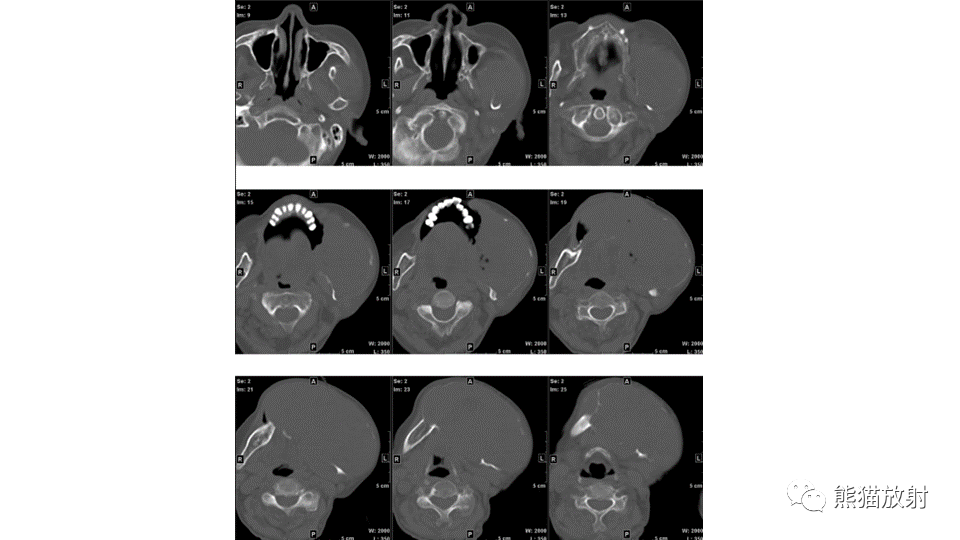

【病例】下颌骨成釉细胞瘤2例CT-11

【病例】下颌骨成釉细胞瘤2例CT-12

【病例】下颌骨成釉细胞瘤2例CT-13

【病例】下颌骨成釉细胞瘤2例CT-14